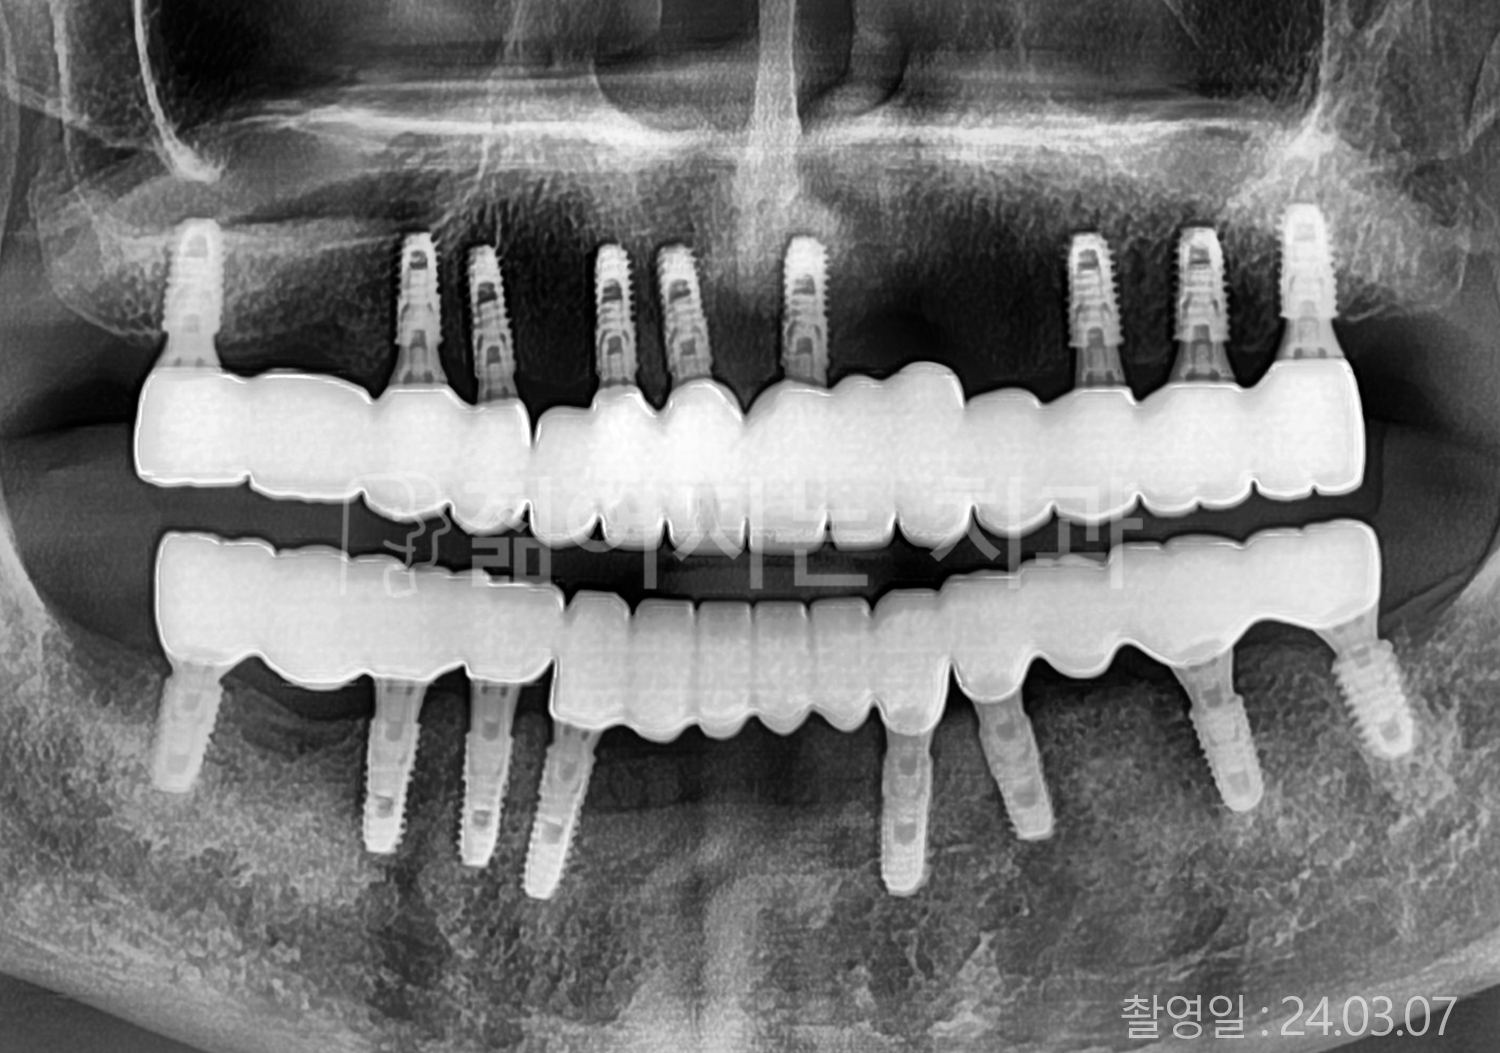

• 70대 고혈압, 당뇨 전체치아 10개 이상 임플란트

• 50대 고혈압, 당뇨 전체치아 10개 이상 임플란트

• 60대 고혈압, 당뇨 전체치아 10개 이상 임플란트

• 50대 전체치아 10개 이상 임플란트

• 70대 당뇨 전체치아 10개 이상 임플란트

• 80대 전체치아 10개 이상 임플란트

• 40대 전체치아 10개 이상 임플란트

• 60대 고협압, 고지혈증 전체치아 10개 이상 임플란트

• 60대 전체치아 10개 이상 임플란트

위 사진의 저작권은 젊어지는 치과에 있습니다.

* 위 사진은 동일 조건에서 촬영 되었습니다. / 모든 치료에는 부작용이 발생할 수 있습니다.